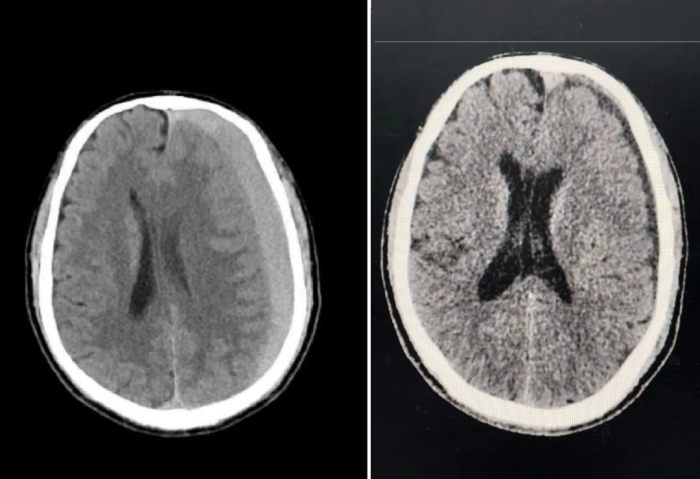

据悉,患者1个月前因颅脑外伤于其他医院治疗后好转出院。然而1个月后复查,通过颅脑CT发现亚急性期硬膜下血肿,为寻求更好的诊治,患者选择到中山一院贵州医院寻求更专业的治疗。

接诊后,神经外科主任医师向欣团队结合检查发现患者颅内血肿量较大,中线结构明显偏移,非手术治疗已无法清除血肿,手术指征明显。经团队讨论,迅速制定了急诊手术方案,为患者在急诊下行微创钻孔引流术,手术过程十分顺利,在紧急并有条不紊的情况下,保障了患者生命安全。术后,在医护人员精心的护理和关怀下患者恢复良好,第二天便能下床自如活动,最后患者康复出院。

亚急性硬膜下血肿

亚急性硬膜下血肿是指受伤后3天至3周内发生的颅内出血血液积聚在硬脑膜下方的血肿。这类血肿大多由于颅脑外伤引起,如车祸伤、摔伤等。脑萎缩、长期使用抗血小板药物、抗凝药物也会诱发此病。

亚急性硬膜下血肿发病较为隐匿,患者可能会出现头痛头晕、认知功能受损、情感淡漠等症状,通常伴有意识障碍。如何治疗取决于出血量及患者的一般情况。